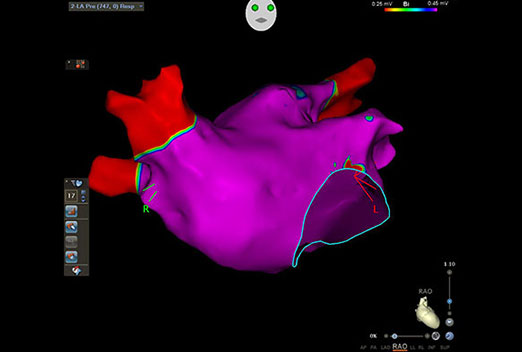

We have a some latest projects photos and Videos. this gallery explain different

health issues related to heart and more information for heart patients thats ill we help for your health improve.